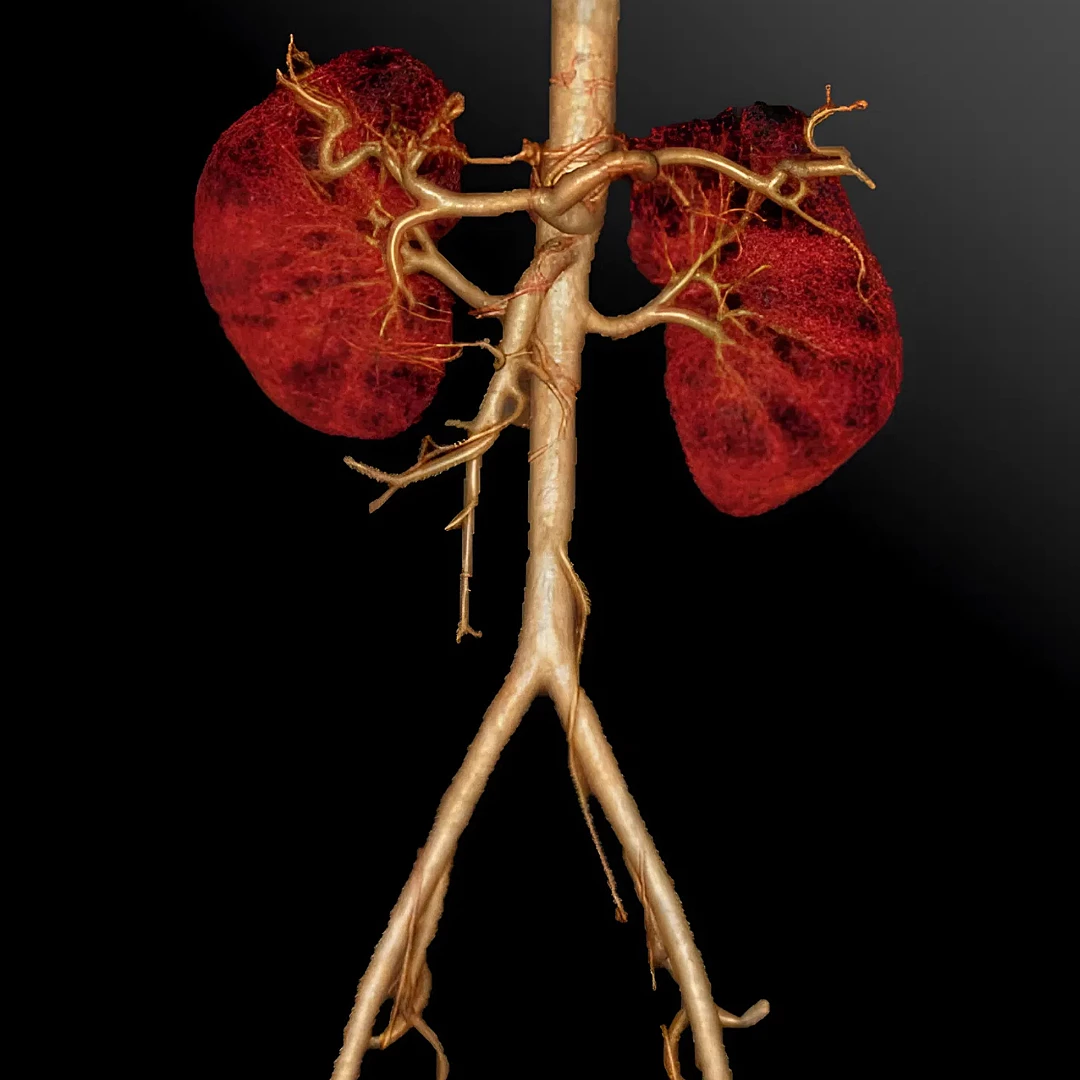

Aortic & Peripheral CT Angiography

Aortic and Peripheral CT Angiography visualizes blood vessels in the aorta and limbs to detect aneurysms, blockages, or vascular disease. It’s a fast, contrast-enhanced scan offering precise vascular assessment for diagnosis and treatment planning.